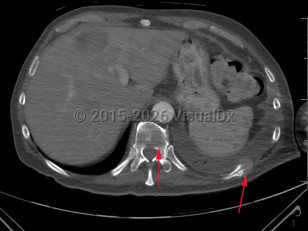

A fracture that occurs from an underlying disease process that has weakened the bone, eg, cancer metastasis to bone, bone cysts, Paget disease, hyperparathyroidism, and osteoporosis. Pathologic fractures typically present with severe, localized pain after a very mild traumatic event, although they can occur with no trauma. Vertebrae and proximal long bones are the most common sites for pathologic fractures.

Pathologic fractures are sometimes the first presenting symptom of malignancy, though they most often occur in patients with a known primary cancer. Most pathologic fractures will require surgical intervention. Pathologic fractures due to malignancy are typically also treated with chemotherapy or radiation.